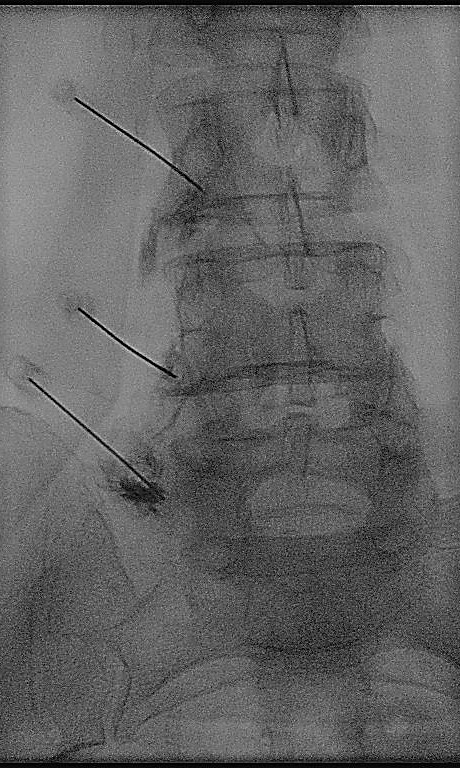

Ασθενής με ιερολαγονίτιδα και δισκοκήλη

Ασθενής 37 χρονών με ιερολαγονίτιδα και άλγος χαμηλά στη σπονδυλική στήλη λόγω συνυπάρχουσας δισκοκήλης. Υπεβλήθη σε έγχυση στην ιερολαγόνιο άρθρωση και στο επίπεδο που πιέζονταν η ρίζα από την κήλη. Άμεση ανακούφιση των συμπτωμάτων με αποτέλεσμα που διαρκεί 3 χρόνια μετά.